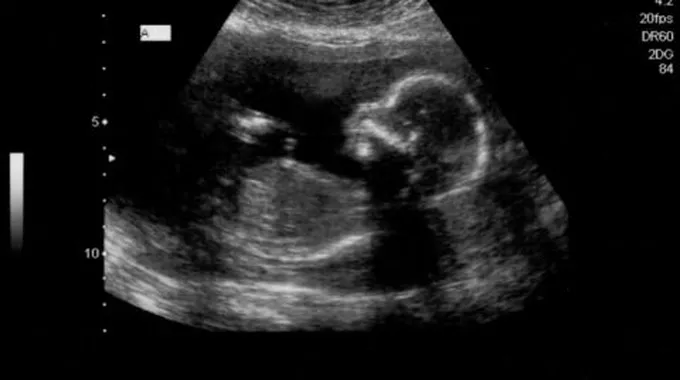

الجنين في الأسبوع السابع عشر

على الرغم من كل المتاعب التي تمر بها المرأة خلال فترة حملها سواء إن كانت صحية أو نفسية، إلّا أنّها تعتبر أجمل مراحل حياتها ابتداءً من اللحظة التي تكتشف فيها بأنّها حامل إلى حين ولادة طفلها ومشاهدته يتنفس بين يديها، والحمل الطبيعي هو الذي تكون مدته تسعة أشهر، ولكبل شهر منها تطورات مختلفة تطرأ على الأم والجنين، فكيف يكون الجنين في الأسبوع السابع عشر من الحمل وما هي التغيرات التي تطرأ عليه وعلى والدته في هذا الأسبوع؟[1]

- يبلغ طول الجنين في هذا الأسبوع ما يقارب 13 سم، أمّا وزنه فيصل إلى 140 غرام تقريباً.